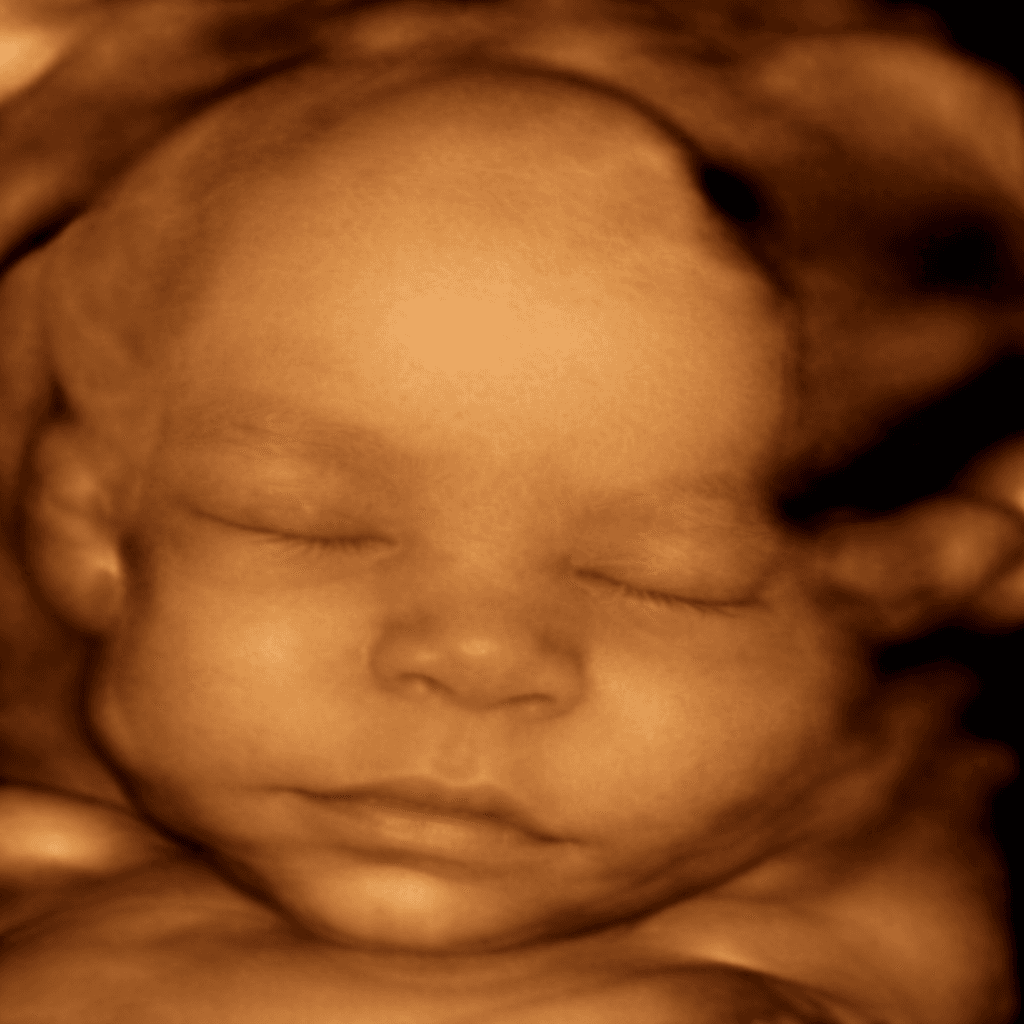

Vuốt để xem sự khác biệt giữa ảnh siêu âm gốc và hình ảnh AI làm nét

Công nghệ AI của LovelyBaby phân tích cấu trúc xương, làm rõ nét từng đường nét chân thực nhất trên khuôn mặt bé để tạo nên bức ảnh kỷ niệm tuyệt đẹp theo bạn suốt đời.